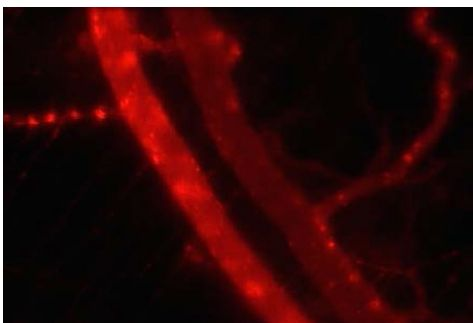

将荧光物质视为model drug,在荧光下观察微气泡的药物动力学。图7为在小鼠window chamber模型下观测Tracer随血液动力学与分布。

图7在Window Chamber Model注射Tracer,观察药物动力学

Figure 7 Pharmacokinetic Analysis of Tracer in Mice Window Chamber Model